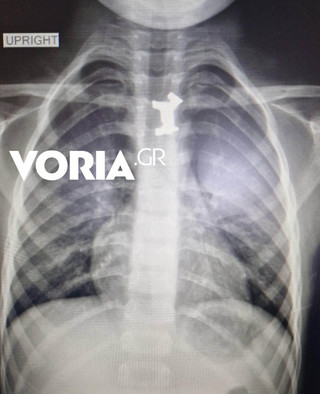

Όπως αναφέρει το voria.gr, μετά από τις ακτινογραφίες και τις απεικονιστικές εξετάσεις διαπιστώθηκε πως το παιδί είχε καταπιεί ένα μεταλλικό σκυλάκι, από γνωστό επιτραπέζιο παιχνίδι που έπρεπε να αφαιρεθεί άμεσα, καθώς ήταν σε αρκετά δύσκολο σημείο.

Αφότου έγιναν όλες οι απαραίτητες εξετάσεις για τον ακριβή εντοπισμό του αντικειμένου, αλλά και μετά από εκτίμηση παιδο-ΩΡΛ, υπεβλήθη σήμερα το πρωί σε οισοφαγοσκόπηση -πρόκειται για μέθοδο αντιμετώπισης οξέων αποφράξεων του ανώτερου πεπτικού στα παιδιά- υπό γενική αναισθησία για την αφαίρεσή του από τον οισοφάγο.